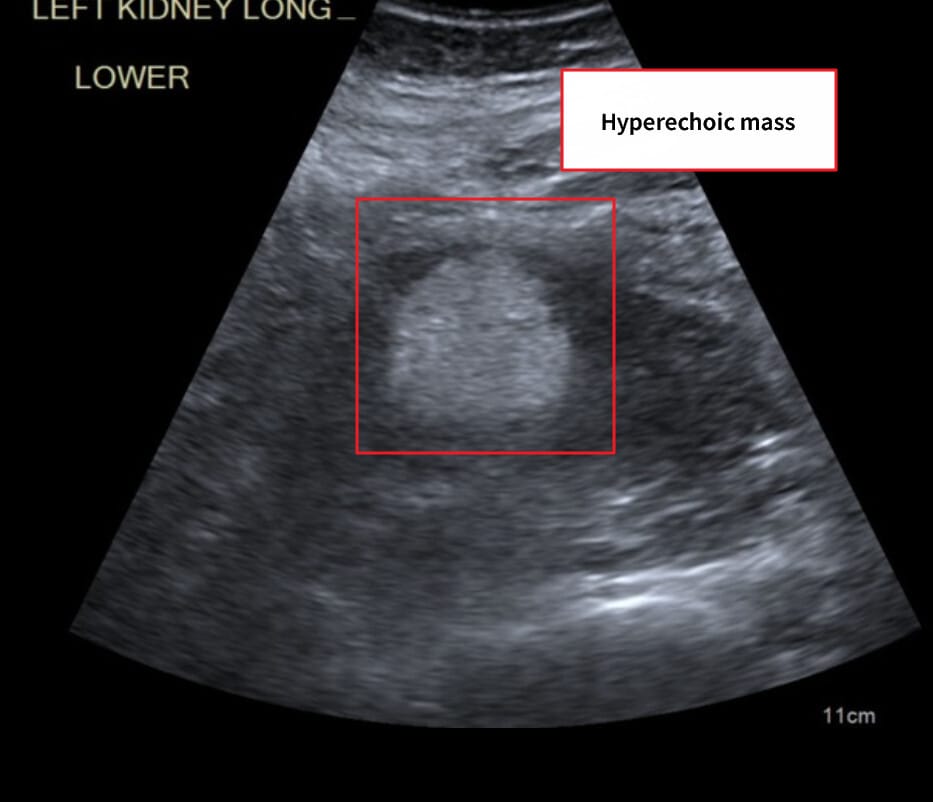

[진단]

– CT/MRI에서 지방 성분(−HU) 확인

Schubert R, Renal angiomyolipoma. Case study, Radiopaedia.org (Accessed on 19 May 2025) https://doi.org/10.53347/rID-16842